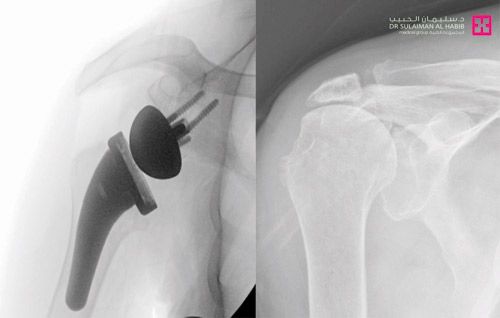

واستطرد د. حمدان موضحاً أن الفريق الطبي خلص إلى أن التدخل المناسب للحالة هو استبدال مفصل الكتف. وبعد اتخاذ الترتيبات اللازمة، أجريت للمريض عملية جراحية نوعية، تم فيها تنظيف محيط المفصل القديم من التكلسات والزوائد العظمية المسببة للاحتكاكات، ومن ثم تركيب المفصل الصناعي الجديد الذي يناسب الحالة، ويتميز بجودته العالية، إذ يساعد في تحقيق المرونة الكاملة للمفصل ومجال أكبر للحركة، واستمرت العملية نحو ساعتين، وتكللت بالنجاح التام. وبعد ذلك تم البدء في تطبيق برنامج العلاج الطبيعي المكثف، ومن ثم غادر المريض المستشفى إلى منزله بعد «3» أيام وهو بصحة جيدة، وتوقع د. حمدان أن تختفي الأعراض بعد الانتهاء من برنامج العلاج الطبيعي، وسيعود لممارسة حياته بصورة طبيعية.